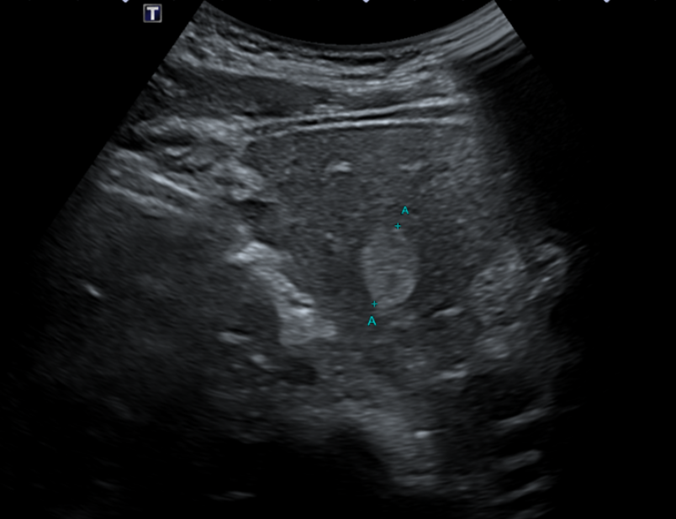

복부초음파상에서 왼쪽 간엽에 1.7cm크기의 고에코 결절이 발견되었습니다. 추가적인 정밀 확인을 위해 복부CT검사를 시행하였습니다. 복부CT에서 왼쪽간엽에 초음파에서 보이는 부분으로 약 1.7cm크기의 혈관종으로 생각되는 병변을 확인할 수 있었습니다.

한마디: 혈관종은 간에서 발견되는 흔한 양성질환으로 초음파를 통해 추적관찰을 하기로 하였습니다. 다만 만성 간 질환이 있거나 간암, 악성 종양의 병력이 있는 경우 혈관종과 유사하게 보일 수 있어 임상적인 추적 검사가 필요합니다.

검사 결과 이미지